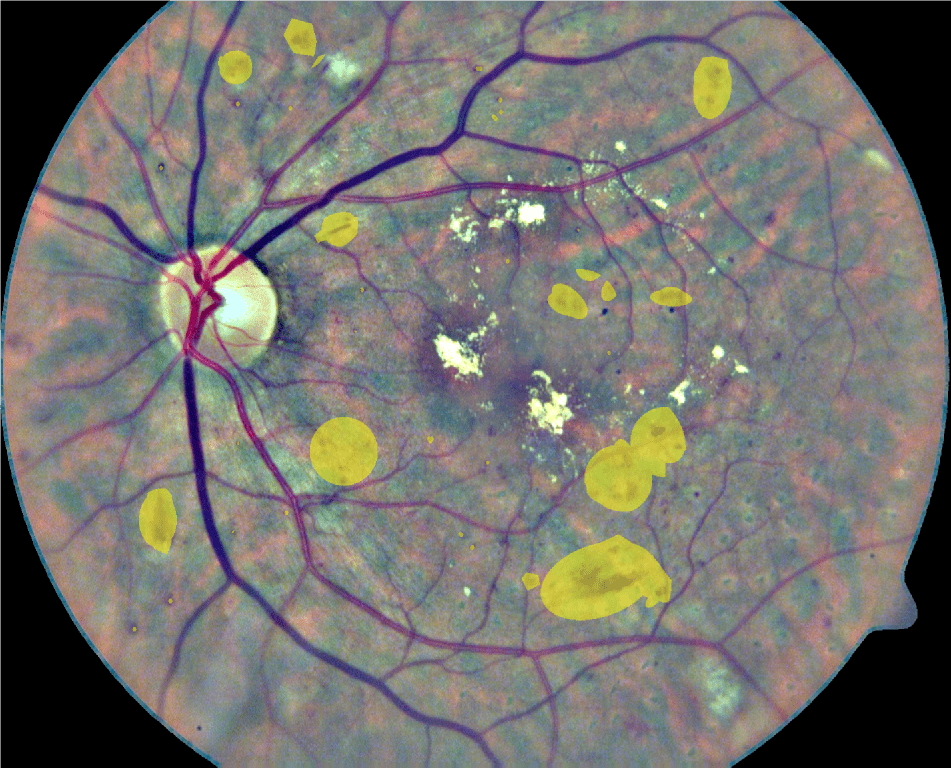

In its early stages, DR might be clinically asymptomatic (Abràmoff et al., 2010). As a consequence, this condition is typically identified when it is more advanced and treatments are significantly less effective (Mookiah et al., 2013). A recent study has shown that 44% of hospitalized patients with diabetes remain undiagnosed (Kovarik et al., 2016). To prevent this, people suffering from diabetes are usually recommended to be regularly examined through fundus images to verify the non-existence of red lesions (Abràmoff et al., 2010). Although fundus photographs are currently the most economical non-invasive imaging technique for this purpose, manual diagnosis requires an intensive effort to screen the images (Mookiah et al., 2013). Red lesions appear as small red dots that might be subtle and too small to be detected at first glance (Figure 1). Large HEs, on the contrary, are more evident and less difficult to visualize.

Refer to caption

Figure 1: Examples of red lesions observed in fundus photographs from DIARETDB1 (Kauppi et al., 2007).